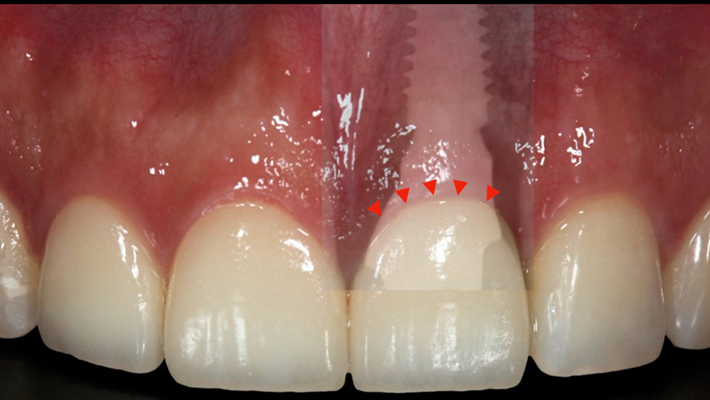

Clinical case: Extraction, immediate placement & loading using

R2GATE solution in aesthetic zone

- Courtesy of Dr. Jong-Cheol Kim, Korea-

Dr. Jong Cheol Kim, immediate loading, digital guided surgery, Digital ONE-DAY Implant, maxillary anterior, #21, guided surgery, immediate loading, AnyRidge, R2GATE, Mega ISQ, MEG Torq, R2GATE Full Surgical Kit

AnyRidge implant system, R2 Guide, R2GATE Full Surgical Kit, Mega ISQ